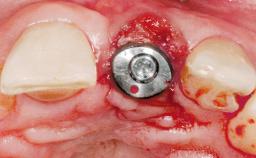

Immediate Flapless Placement of an Implant in a Maxillary Left Central Incisor Site

A 29-year-old female patient presented for treatment to replace the upper left central incisor tooth with an implant- supported restoration. The tooth had been intermittently symptomatic for the previous 12 months. The tooth had originally suffered trauma about 15 years previously. Several endodontic treatments had been performed, including an apicectomy procedure to retain the tooth. The patient was healthy and a non-smoker. She had reasonable expectations in regard to esthetic outcomes and the risk of marginal tissue recession following treatment. At medium smile, the gingival margins of the upper teeth were visible, with a display of 3 to 4 mm of the gingival margins. Gingival recession of tooth 21 and a discrepancy in the gingival levels between teeth 11 and 21 was observable during normal speech and smile.

Placement Protocol Immediate implant placement

Tooth Site Maxillary incisor or canine

Socket Morphology Single-root socket

Socket Integrity Damage to one or more bone walls

Bone Volume Damage to one or more socket walls

Type of Implants One-Piece